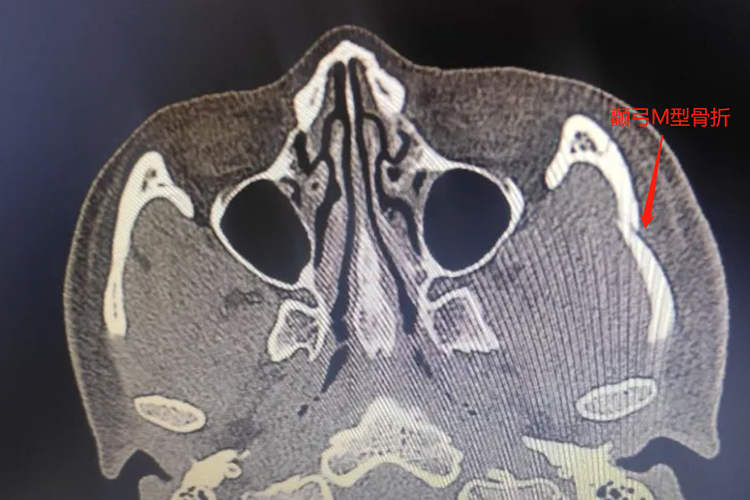

颧弓骨折M型主要表现为颧骨中部向后下移位,颧部骨折段明显内陷,外形改变消失,颜面不对称,呈“M”型塌陷,影像检查可见颧骨呈“M"型折断。骨折周围组织明显肿胀,并出现张口困难,累及眼眶底部可发生复视,眶下神经损害后,可致患处皮肤颜色迟钝,伴有麻木感,周围可见出血性瘀斑和皮下气肿。

颧弓骨折M型表现为面部出现“M”型塌陷,可伴有周围组织肿胀、疼痛、张口受限等情况,多是由于侧方的垂直力量打击所致。